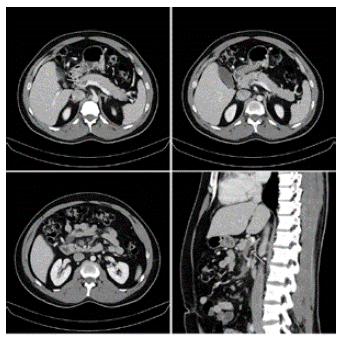

El paciente ingresa por segunda vez al servicio de urgencias diez días después del accidente, refiriendo cuatro días de náuseas constantes, distensión abdominal, dolor tipo cólico en epigastrio e hipocondrio derecho, de predominio postprandial, gravativo y que empeora con los cambios de posición en el decúbito. Al examen físico sus signos vitales eran normales, no se evidenciaban estigmas de trauma toracoabdominal pero la palpación del abdomen superior era notablemente dolorosa, por lo que se decidió realizar una tomografía computarizada (TC) de abdomen total con contraste endovenoso. En la misma se documenta trombosis de la vena mesentérica superior y de la rama distal de la porta derecha, sin evidencia de lesiones traumáticas en órganos sólidos ni vísceras huecas (figura 1).

Actualmente se considera la TC con contraste venoso como el método diagnóstico de elección, debido a sus costos más bajos en comparación con la resonancia magnética, su amplia disponibilidad y su excelente sensibilidad3-5,13. Los hallazgos tomográficos incluyen asas intestinales dilatadas y engrosadas, estriación de la grasa mesentérica, ascitis, un halo o aspecto blanco del intestino, defectos de llenado de los vasos y neumatosis intestinal3,5,15. La TC presenta como ventajas el no ser operador dependiente, la posibilidad de identificar otras lesiones asociadas, así como la extensión exacta de la trombosis, y detectar signos de isquemia intestinal 8,18.

La realización de la TC abdominal con contraste venoso en el caso discutido se considera acertada pues este es el estándar de oro para el diagnóstico de TVPM4. Lo anterior permitió identificar la etiología del dolor abdominal y el inicio oportuno de la terapia anticoagulante.